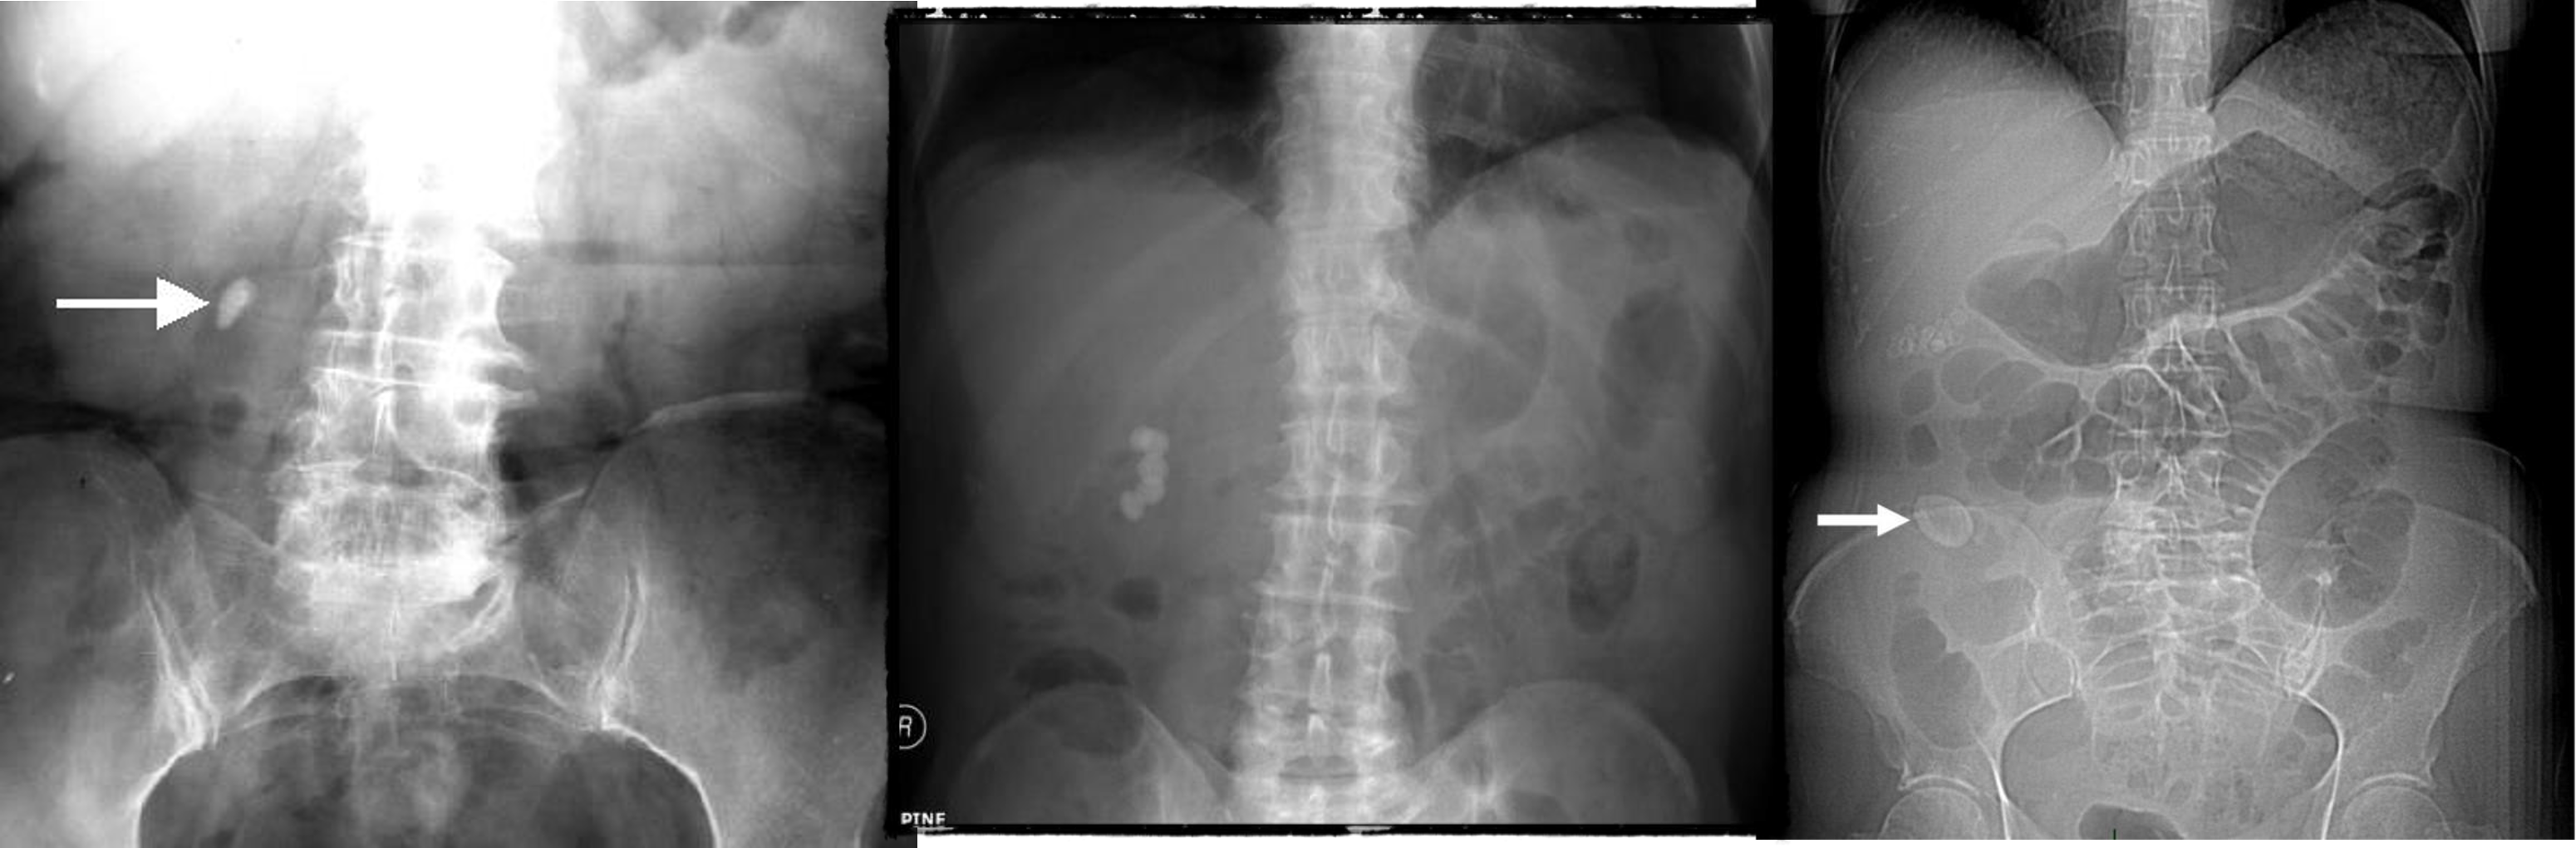

- Uretic stone

- radioopaque shadow on RUQ - renal stone

- Gallstone illeus - radioopaque shadow (regulars triad??)

- & 2 Appendicitis - appendicolith/feacolith in young, MALT GALT